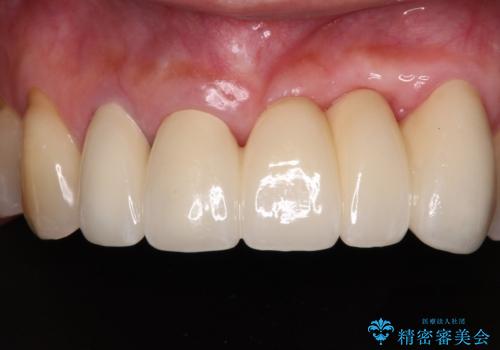

- 前歯の歯肉の腫れを気にして来院された患者様です。

前歯のみならず、奥歯の銀歯や下顎前歯のデコボコなど、色々と気になる部分を治したいとのことでした。

前歯は抜歯が必要であったので、抜歯を行い、その後歯肉移植をおこなった上でオールセラミックブリッジによる補綴治療を行うこととしました。

気になっている部分を全て治療したことで、費用はかかりましたが、仕上がりには大変満足していただき、治療をおこなって良かったと仰っていただきました。